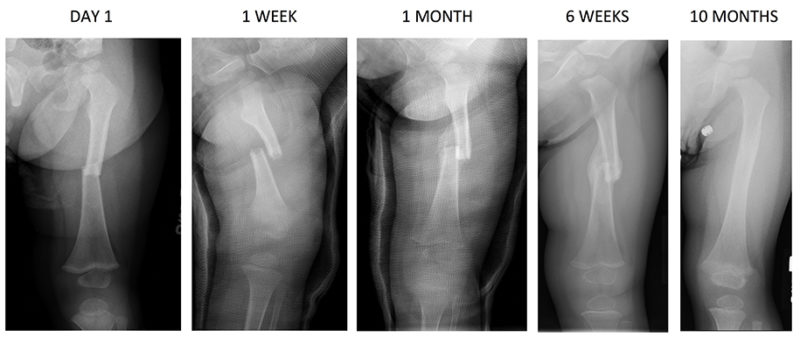

Image

Intramedullary nailing is the gold standard for diaphyseal fractures of the femur and tibia. It is a load-sharing device inserted via a remote entry portal (e.g., the piriformis fossa or greater trochanter for the femur). Reaming the medullary canal generates autologous bone graft that is deposited at the fracture site, stimulating osteogenesis. The nail acts as an internal splint, allowing controlled axial micromotion while resisting bending and torsion. This micromotion generates the ideal strain environment (two to ten percent) to stimulate robust soft and hard callus formation.

Minimally Invasive Plate Osteosynthesis (MIPO) is another application of relative stability. A long bridge plate is slid submuscularly and extraperiosteally across the comminuted fracture zone. Screws are placed only in the proximal and distal main fragments. By leaving the fracture zone entirely untouched, the fracture hematoma and periosteal blood supply are preserved. The working length of the plate (the distance between the two closest screws across the fracture) is intentionally kept long to increase the flexibility of the construct, thereby promoting secondary healing.